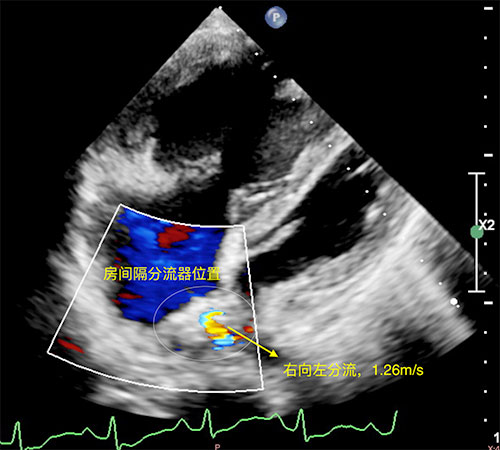

患者出院前超声心动图,图中示意房间隔造孔支架系统及右向左分流束